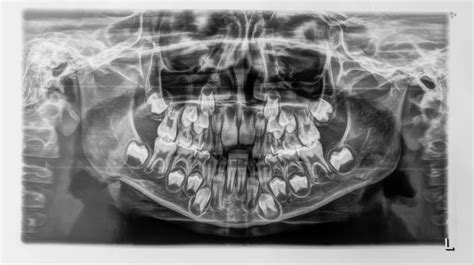

¿Cuántos dientes de leche tiene un niño?

Si te preguntas cuántos dientes de leche tenemos, la respuesta es 20: 10 dientes de leche en la arcada superior y 10 en la arcada inferior. Estos 10 dientes en el maxilar y 10 en la mandíbula son los que guardarán el espacio para la futura sonrisa de tus hijos. Tras la caída de los primeros dientes empieza el proceso de dentición mixta, en el que conviven dientes deciduos y dientes permanentes.

La caída de los dientes de leche es un momento crucial en el crecimiento de los niños. Entre los 5 y 6 años y hasta los 12 años es cuando se caen los dientes de leche. Durante este tiempo, los dientes temporales conviven con los dientes definitivos. Normalmente a los 12 años los niños ya completan su dentadura, pasando de 20 dientes temporales a 28 dientes adultos, a falta de las 4 muelas del juicio que crecen más tarde.

La diferencia entre los dientes de leche y los dientes definitivos reside principalmente en la cantidad de dientes, en su anatomía y en su composición. En cuanto a la cantidad, como ya mencionamos anteriormente, los dientes deciduos son 20, mientras que los permanentes son 32 (si tenemos en cuenta las muelas del juicio).